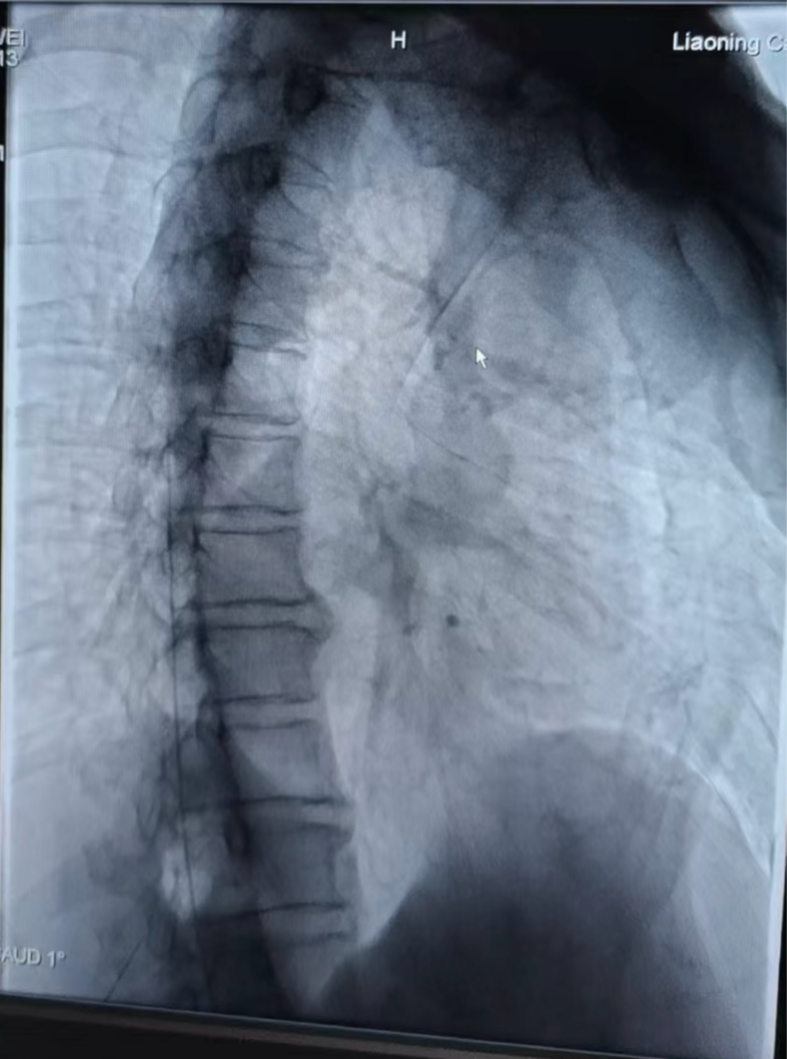

图2 术中导管影像